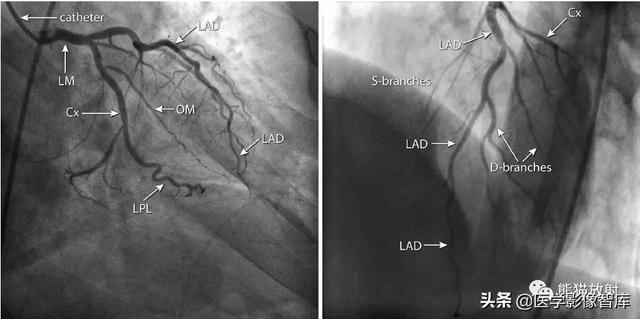

为了与CT比较,图6和图7显示有创性冠状动脉造影的解剖切面。有创性血管造影仍然被认为是评价冠状动脉解剖的金标准,具有很高的时间和空间分辨率,而且评价管腔不受钙化的限制。但其主要缺点是有创性操作,尽管并发症的风险很低。

图6 有创性冠状动脉造影在两个不同的方向(左图, 左前斜45°;右图, 右前斜35°) 显示右冠状动脉(RCA) :RV-右室支;RDP-右后降支;RPL-右后侧支;conus-圆锥支

图7 有创性冠状动脉造影在两个不同的方向(左图,右前斜30°,尾位25°;右图,左前斜50°,头位25°)显示左冠状动脉:LM-左冠状动脉主干;LAD-左前降支;Cx-回旋支;OM-钝缘支;LPL-左后侧支;S-branches -间隔支;D-branches -对角支